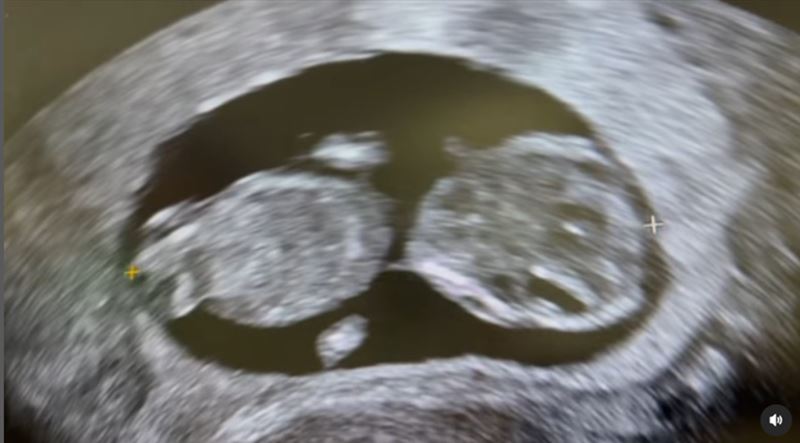

ต้องบอกตรงนี้เลยว่า คุณแม่บุ๋ม ปนัดดา ถือว่าเก่งมาก ๆ ที่แม้ว่าอายุจะ 48 ปีแล้ว แต่ล่าสุดแม่บุ๋ม ปนัดดา ได้ตั้งท้องลูกคนที่ 3 มาแล้วกว่า 5 เดือน และครั้งนี้ก็ได้ลูกผู้ชาย น้องอเล็กซ์ จะได้มีเพื่อนแล้ว

อย่างไรก็ตาม การมีลูกของบุ๋ม ปนัดดา ในครั้งนี้ ไม่ใช่การมีลูกโดยธรรมชาติ แต่บุ๋มได้พึ่งพากระบวนการทางวิทยาศาสตร์ คือทำอิ๊กซี่ (ICSI) กับคลินิกสำหรับผู้มีบุตรยากแห่งหนึ่ง ซึ่งการที่บุ๋มตั้งท้องในวัยเกือบ 50 ปีแบบนี้ เจ้าตัวก็ยอมรับว่ามีความเสี่ยง ในช่วง 3 เดือนแรก น้องดิ้นเก่งมาก แต่ที่ไม่ได้ประกาศเพราะมีเลือดออก และบุ๋มก็ต้องการมั่นใจว่าลูกจะไม่หลุด จะอยู่กับเรา พร้อมขอบคุณคุณหมอและทีมงานที่ชัดเจนและไม่เลี้ยงไข้ ได้ลูกหรือไม่ ก็บอกกันตรง ๆ